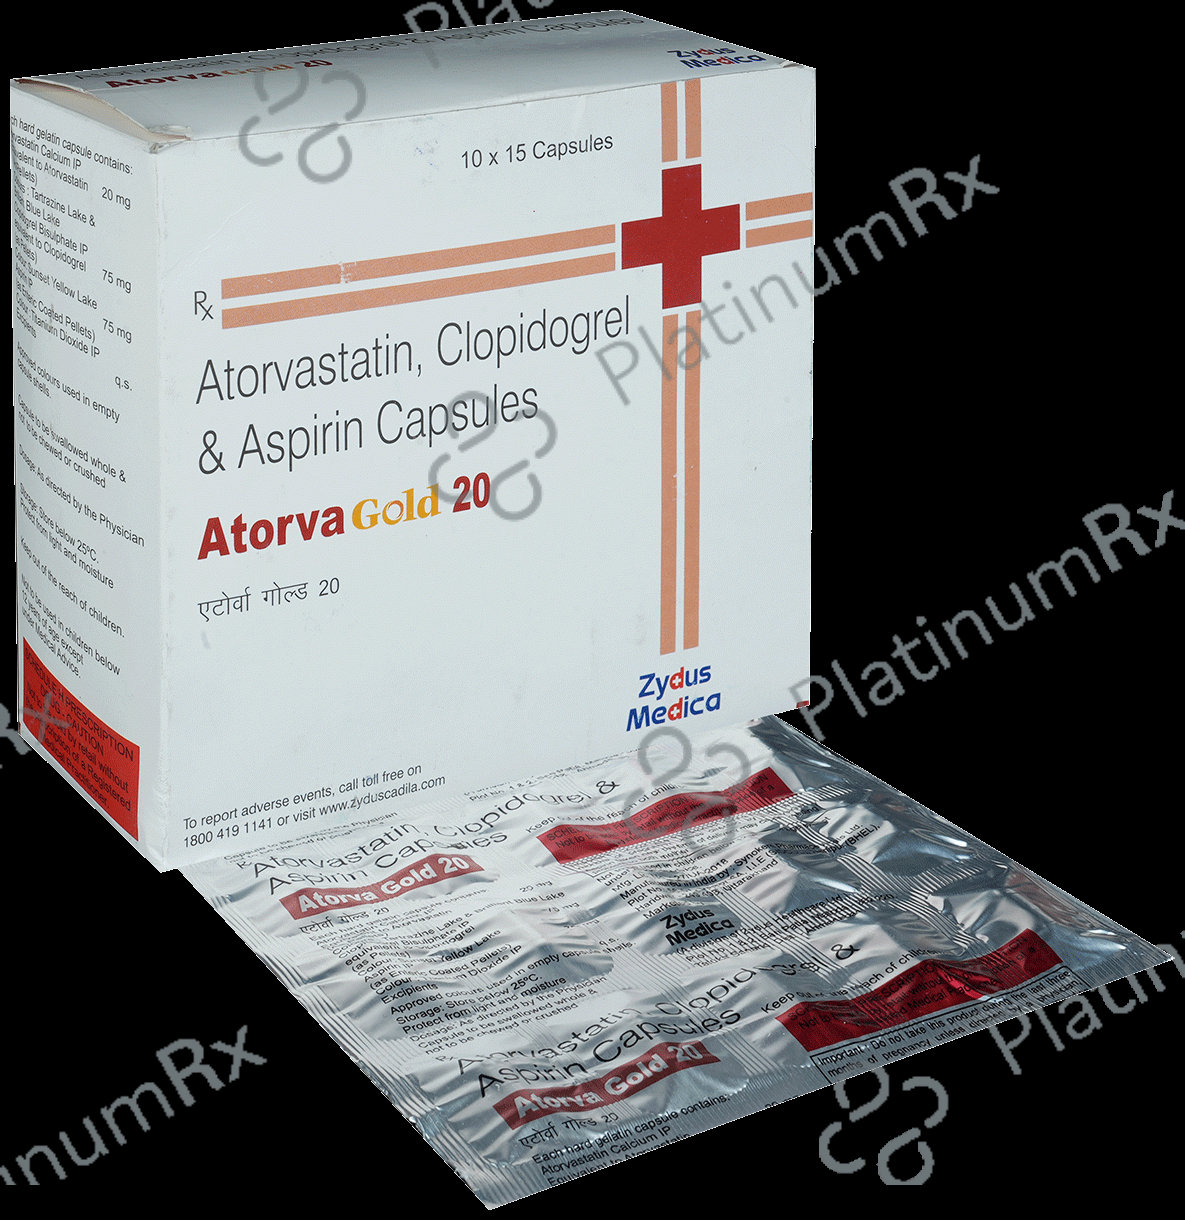

Aspirin 75mg + Atorvastatin 20mg + Clopidogrel 75mg

Salt CompositionAspirin 75mg + Atorvastatin 20mg + Clopidogrel 75mg (same for both)

Atorva Gold 20/75/75mg Capsule 15s

Atorva Gold 20/75/75mg Capsule 15s

Zydus Cadila

₹141.1